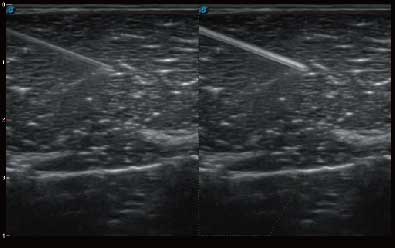

自动识别组织边界信息进行图像无损拼接 抖动抑制技术提高成像效果 完整显示较大病灶及组织,为临床提供可靠诊疗方案